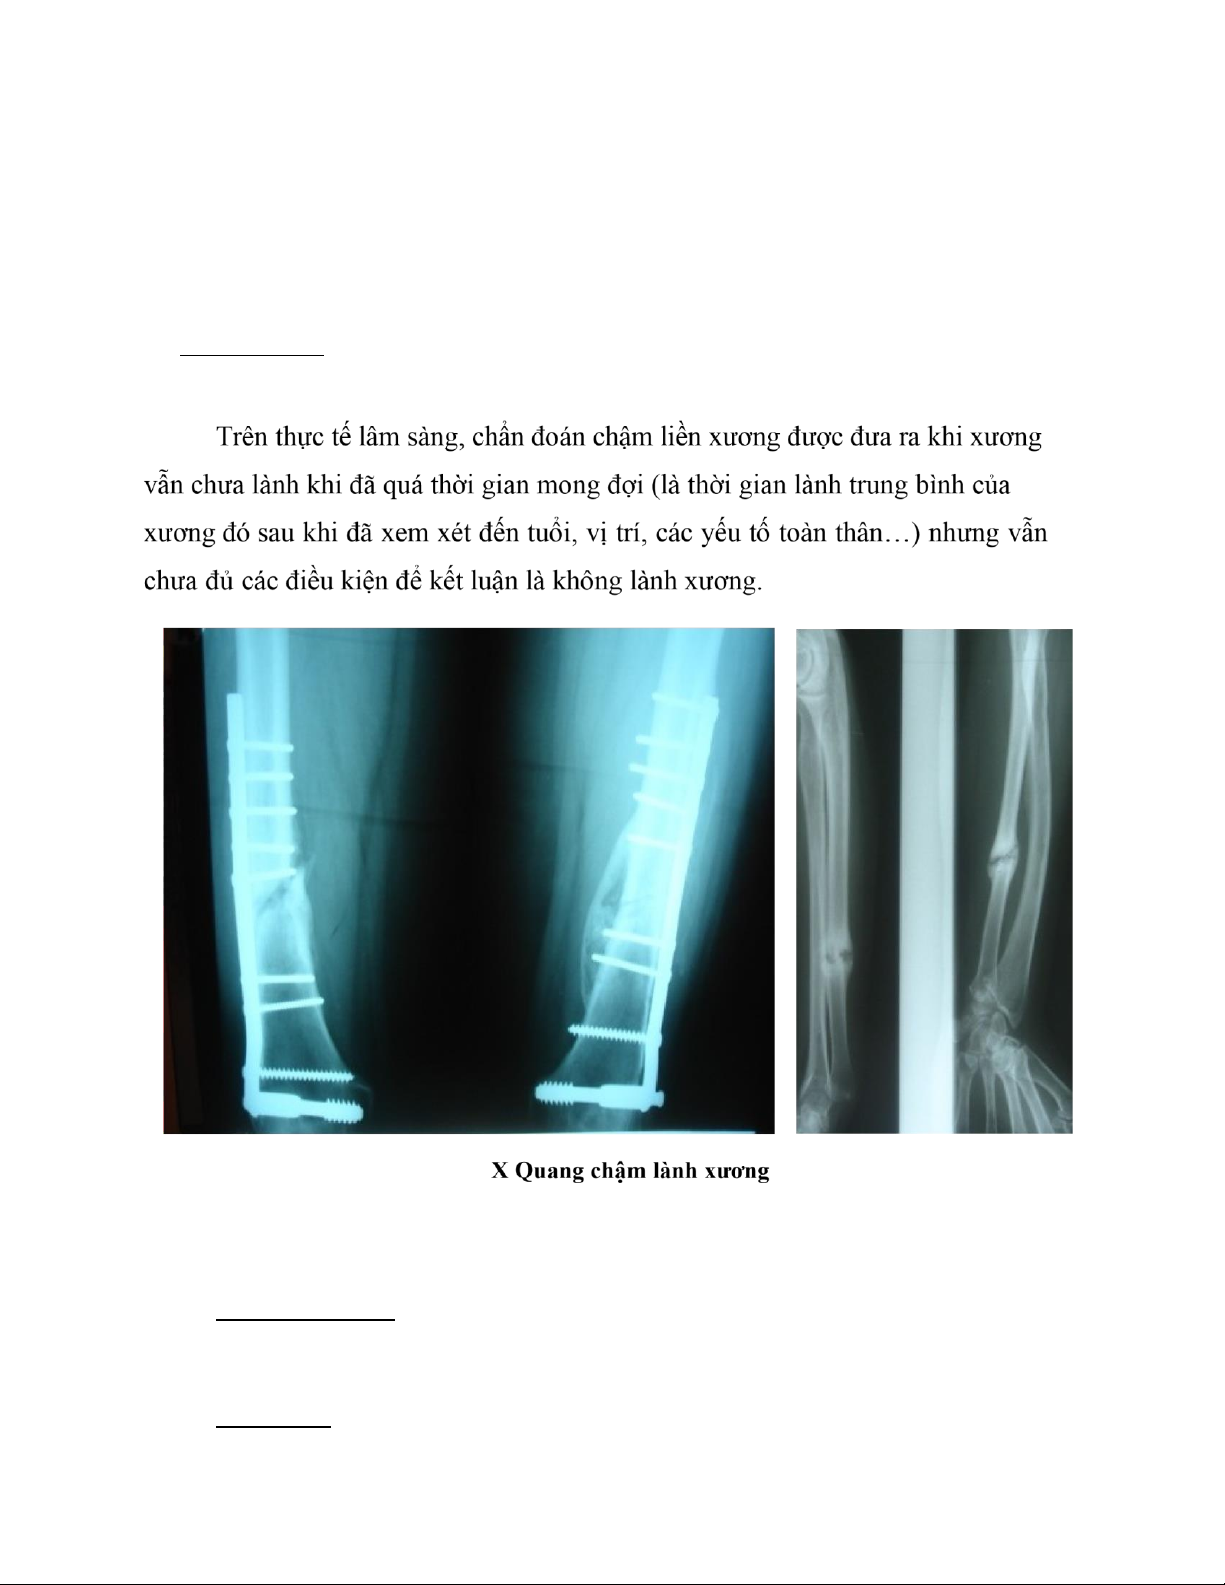

2.4.2. Chẩn đoán chậm liền xương: L â m s àn g:

· Đau dai dẵng tại ổ gãy · Ổ gãy không vững lOMoAR cPSD| 39651089

· Không chịu lực được · Teo cơ

X-q uan g cho thấy có cal bắt cầu nhưng còn khe gãy và ống tủy các đầu gãy không bị bít kín lại.